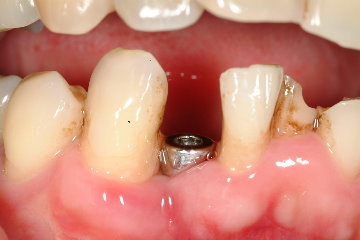

圖三為拔牙後的完整骨槽骨形狀,圖四為使用之Omni Tight人工植牙體,圖五為立即植牙後的情形,這時流血已完全停止,而齒槽骨與人工植第之縫隙再使用合成人工骨粉修復之,圖六為一週後牙肉之恢復情況

圖六 |